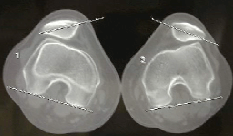

La photo ci-dessous montre le cartilage de la rotule en haut, celui de la trochlée en bas. C'est une vue sous arthroscopie; le genou est gonflé avec du sérum physiologique, éloignant les deux cartilages. La rotule glisse sur le fémur (leurs cartilages). A côté, c'est la coupe en IRM de la même vue où les deux cartilages sont au contact.